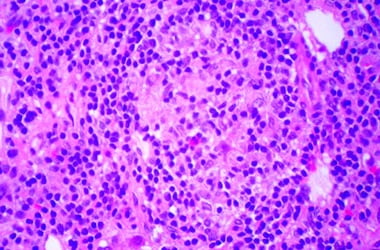

Сначала под влиянием неких причин лимфоциты начинают уничтожать клетки желчных протоков — в них формируется воспалительный процесс. Вследствие воспаления нарушается проходимость протоков и развивается застой желчи. В этих участках происходит повреждение гепатоцитов и снова развивается воспаление. Массовая гибель клеток способна привести к формированию цирроза.

Первичный БЦП — аутоиммунное заболевание, которое проявляется как хроническое негнойное деструктивное воспаление желчных протоков (холангит). На поздних стадиях оно вызывает застой желчи в протоках (холестаз) и со временем провоцирует развитие цирроза печени. Чаще всего от патологии страдают женщины сорока-шестидесяти лет.

- III стадия. Гепатоциты — клетки печени — начинают преобразовываться в соединительную ткань, формируются спайки-рубцы, которые «сближают» между собой желчные протоки.